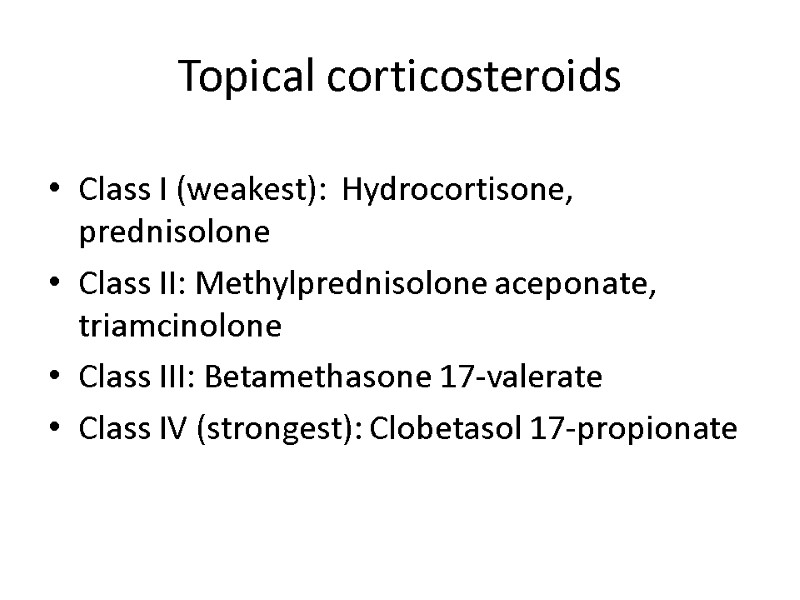

Topical corticosteroids Class I (weakest): Hydrocortisone, prednisolone Class II: Methylprednisolone aceponate, triamcinolone Class III: Betamethasone 17-valerate Class IV (strongest): Clobetasol 17-propionate